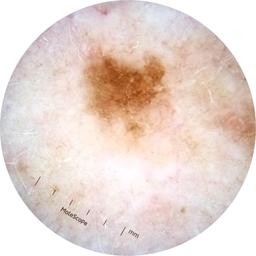

MEL-SELF - Dermoscopic

- Name: MEL-SELF - Dermoscopic

Description:

Dermoscopic lesion images (close-up views of benign and malignant lesions) from the MEL-SELF trial (the Melanoma Self Surveillance trial).